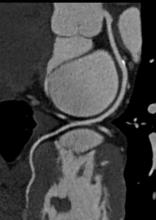

Atherectomy devices are used in the cath lab to debulk lesions by cutting or laser ablating plaque, calcium and tissue hyperplasia from vessel walls, allowing recanalization of the vessel lumen as an end in itself, or in preparation for stenting. While some devices have an indication for the coronaries, the primary use of these devices is forperipheral artery disease (PAD)Â in the legs.Â